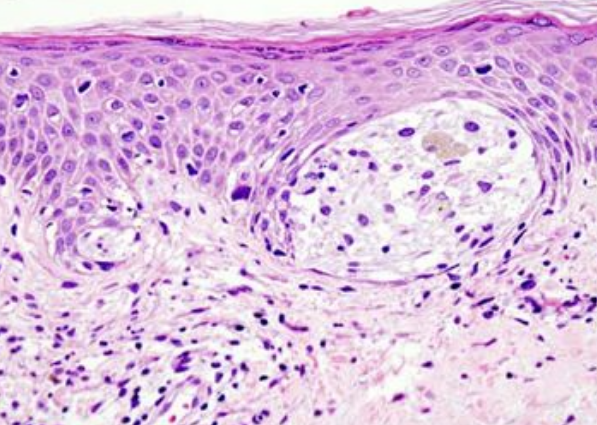

黑色素瘤屬于皮膚腫瘤,多發(fā)于30歲以上的人群,惡性黑色素瘤對人們的健康帶來了嚴重的威脅。美國對于惡性黑色素瘤治療的經(jīng)驗較為豐富。近日,美國一項新研究指出,通過三種先進治療方法聯(lián)合使用可以提高惡性黑色素瘤治療的效果。讓我們一起來看看美國是如何治療惡性黑色素瘤的吧。

在這項新的研究中,Kaufman和他的同事們首先在人黑色素瘤細胞系和黑色素瘤小鼠模型中研究了聯(lián)合使用BRAF抑制劑維羅非尼(vemurafenib)和T-VEC的潛力。盡管這種聯(lián)合使用導致對BRAF發(fā)生突變的人黑色素瘤細胞系的殺傷能力增強,但是這些研究人員吃驚地發(fā)現(xiàn)聯(lián)合使用T-VEC和MEK抑制劑曲美替尼(trametinib)---較初用作對照---促進發(fā)生BRAF突變的人黑色素瘤細胞系和未發(fā)生BRAF突變的人黑色素瘤細胞系死亡。他們隨后在免疫功能正常的黑色素瘤小鼠模型中驗證了這些改善的治療結果,并鑒定出這種內(nèi)在機制的幾個方面,包括對細胞毒性CD8+ T細胞和一組樹突細胞的依賴性以及以PD-1和PD-L1表達增加為特征的炎性反應產(chǎn)生。

這些研究結果導致這些研究人員嘗試了T-VEC、曲美替尼和一種PD-1靶向單抗的聯(lián)合使用,這導致在黑色素瘤小鼠模型中更加有效地清除腫瘤??傮w而言,雖然單獨使用T-VEC或MEK抑制劑曲美替尼在大約20%的小鼠中產(chǎn)生了治療反應,但是聯(lián)合使用這兩者(即雙重組合)可將治療反應率提高至50%,聯(lián)合使用這三者(即三重組合)可將治療反應率提高至將近滿分。他們還在結腸癌小鼠模型中測試了這種雙重組合和三重組合,結果觀察到相似的結果---當T-VEC與曲美替尼或抗PD-1藥物聯(lián)合使用時,小鼠的生存率顯著提高,而且這種三重組合完全清除了所有接受治療的小鼠體內(nèi)的腫瘤。